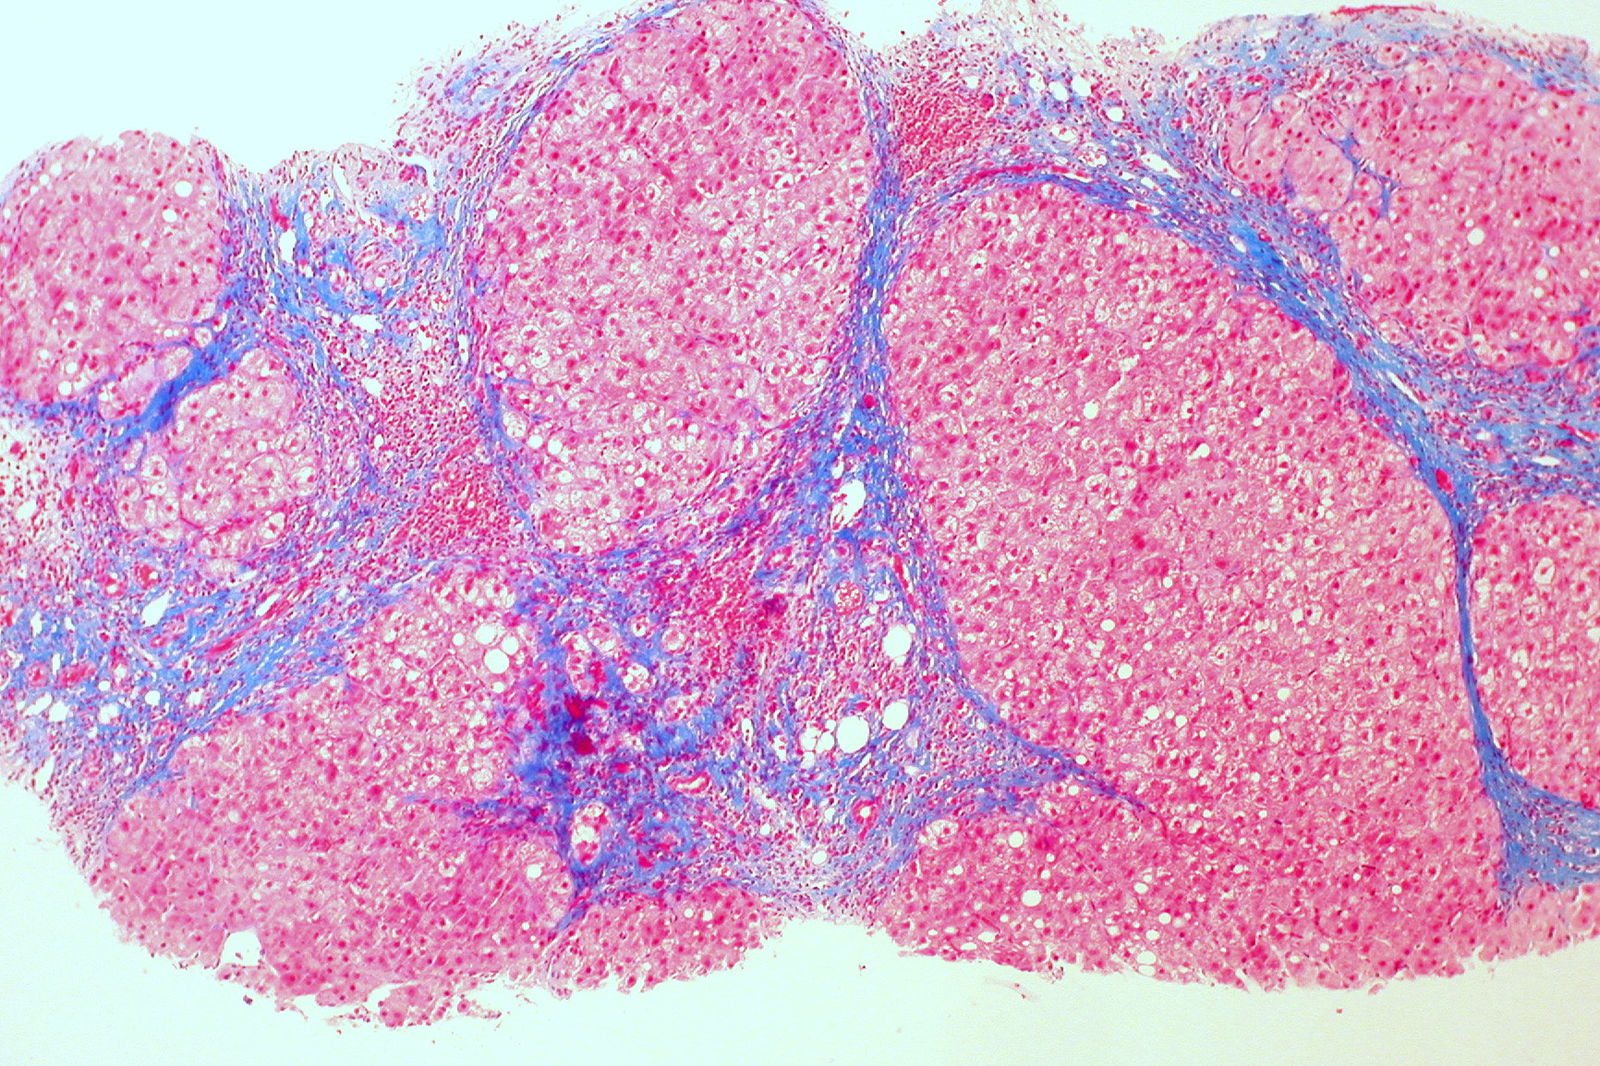

On microscopic examination, there is usually a loss of the normal lobular architecture of the liver. Instead, regenerative nodules are seen, and these are surrounded by fibrous tissue. If these nodules are <3mm, the cirrhosis is described as micronodular, and this is typically seen in alcoholic liver disease and haemochromatosis.

Irregular nodules that are larger than 3mm are given the term macronodular cirrhosis – this is typically seen with hepatitis B, hepatitis C and alpha-1 antitrypsin deficiency.

It is possible to have a mixed micronodular and macronodular pattern as well.

Ed Uthman from Houston, TX, USA, CC BY 2.0 , via Wikimedia Commons

Liver Cirrhosis Microscopy

Here, you can see the collagen in blue i.e. the fibrous septa with regenerating nodules in between.